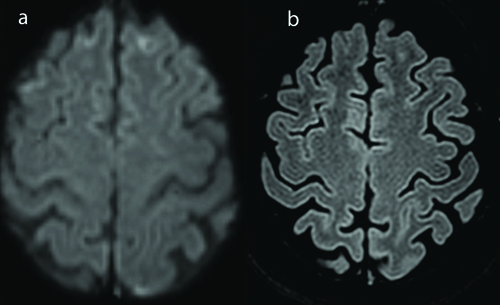

A 45-year-old female patient with no prior comorbidities was admitted with three-day history of high-grade intermittent fever followed by generalised tiredness. There was no history of joint pains, prior headache or seizures. Serology for dengue was positive and she was admitted in the Department of Internal Medicine. She was managed conservatively with hydration and antipyretics. She had drop in platelet counts to less than 10000/μL which required administration of platelet transfusion. Immediately after platelet transfusion, patient developed sudden onset of severe thunderclap headache associated with elevated blood pressures (>160/90 mm). The headache was noted to increase with blood pressure rise. There was no history of weakness of limbs or blurred vision. Clinical examination revealed no focal neurological deficits or meningeal signs. Magnetic Resonance Imaging (MRI) of the brain [Table/Fig-1] showed T2 weighted hyperintensities involving the left occipital and bilateral fronto parietal regions. There was evidence of focal restricted diffusion on Diffusion Weighted Imaging (DWI) sequences and no evidence of contrast enhancement. MR Angio (MRA) [Table/Fig-2] showed evidence of multifocal stenosis and narrowing involving the left vertebral and right posterior cerebral arteries. The scans were discussed with the neuroradiology team and were felt to be suggestive of Posterior Reversible Encephalopathy Syndrome (PRES). The differentials considered were primary CNS angiitis and cerebral venous thrombosis. She was managed with antioedema measures and anti-hypertensive agents-Mannitol at a dose of 0.5 mg/kg/day, hypertonic saline infusion at 15 mL per hour and labetalol 200 mg per day and had complete resolution of symptoms. She was discharged after improvement. At two weeks follow-up, patient was asymptomatic and had no deficits. Repeat MRI done after three months showed complete resolution of the abnormalities seen on the initial scans confirming a diagnosis of PRES [Table/Fig-3].

a) T2 FLAIR and b) Diffusion images showing complete resolution of lesions.